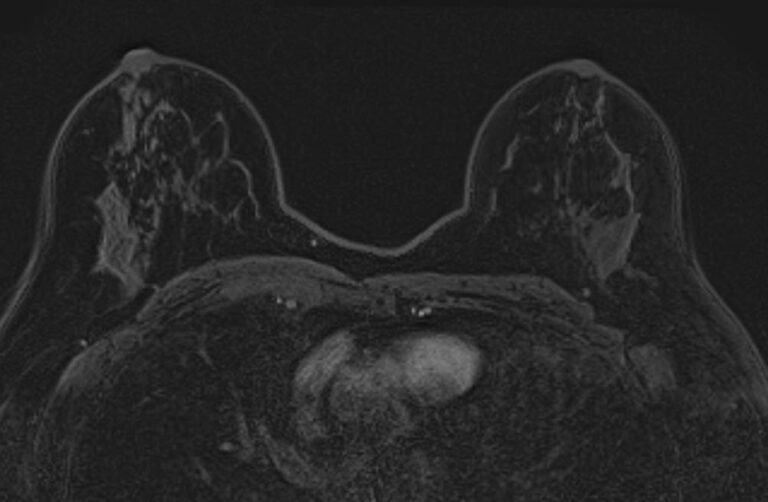

Выполнение МРТ молочных желез без контрастирования возможно для динамического наблюдения состояния имплантатов после пластической операции груди. Во всех остальных случаях во время проведения исследования внутривенно вводится контрастное вещество. Для контрастного усиления применяются препараты на основе солей гадолиния (Магневист, Гадовист и др).

- Для оценки состояния силиконовых имплантов после пластики груди;

- Для динамического наблюдения после операции и в ходе проведения химио- и лучевой терапии рака молочной железы;